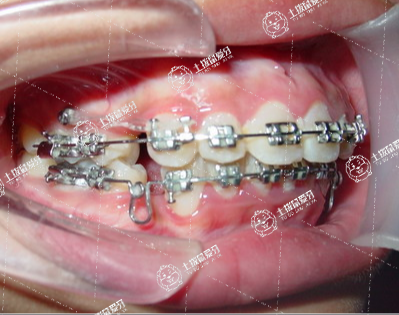

牙列不齊的一般采用的治療辦法,是通過正畸的方式解決,正畸是通過特制鋼絲通過長時間對牙列施加力量,達到排齊牙列的目的?,F(xiàn)在孩子的這個年齡階段是傳統(tǒng)正畸的最佳治療階段,建議到正規(guī)口腔醫(yī)院正畸科。需要制取模型了解治療的方案和費用,一般正畸的時間在一年以上,費用就很難說了。平時不要舔牙齒,不要用手摸,有可能會自行調整過來,如果到12歲,門牙還是突出,這時候需要矯正。